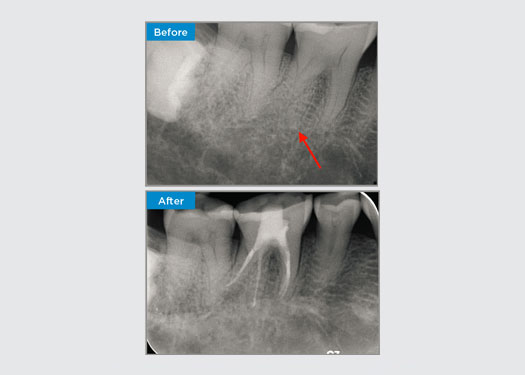

El paciente presentó pulpitis irreversible en la pieza dental 46. A partir de la radiografía preoperatoria, la pieza dental 46 se presenta con una raíz distal adicional (morfología dental Radix Entromolaris). Una escaneo CBCT ha confirmado la presencia de raíz distolingual con curvatura grave de la raíz. Una cuidadosa selección de limas es fundamental para esta raíz distobucal delicada.

Dr. Jack Lin, endodoncista, Sídney, NSW Australia